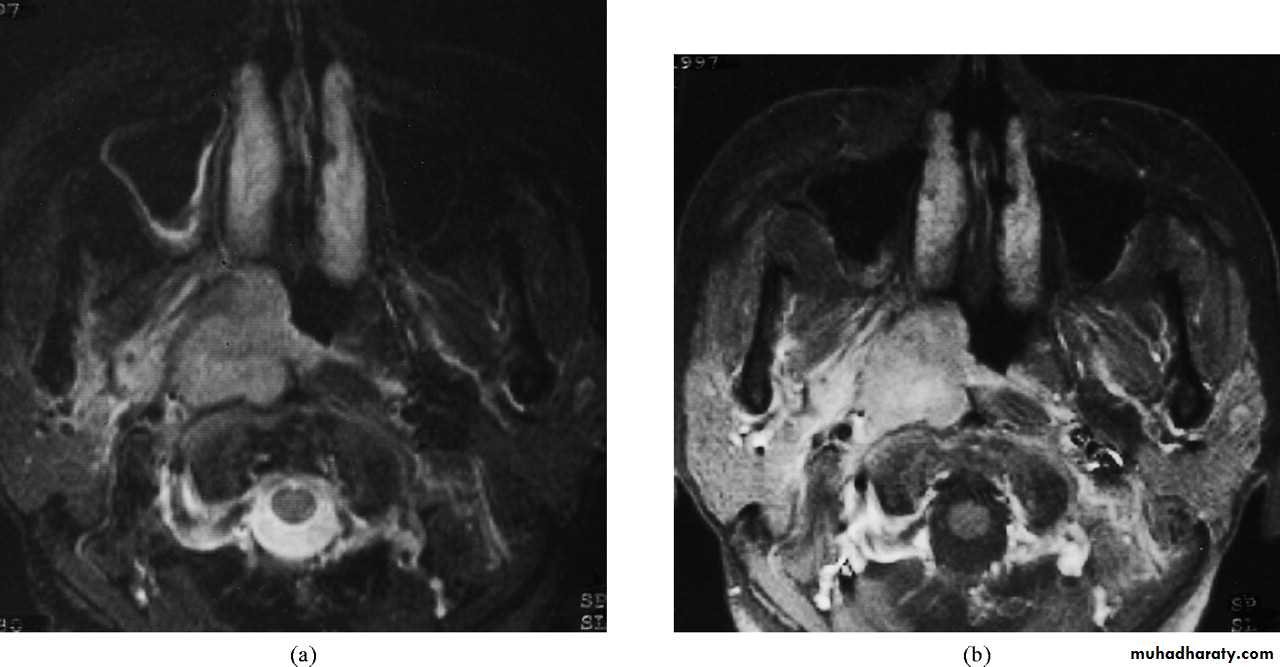

Investigation

1. Imaging:a. X-ray of the base of the skull---- bony destruction involving the petrous bone, foramen lacerum and carotid canal.

b. CT scan and MRI: MRI is superior to CT scan in finding soft tissue involvement.